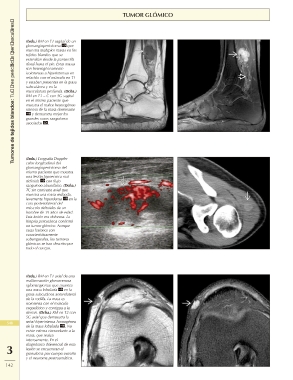

Page 18 - Manaster - Musculoesquelético 2: Enfermedades No Traumáticas